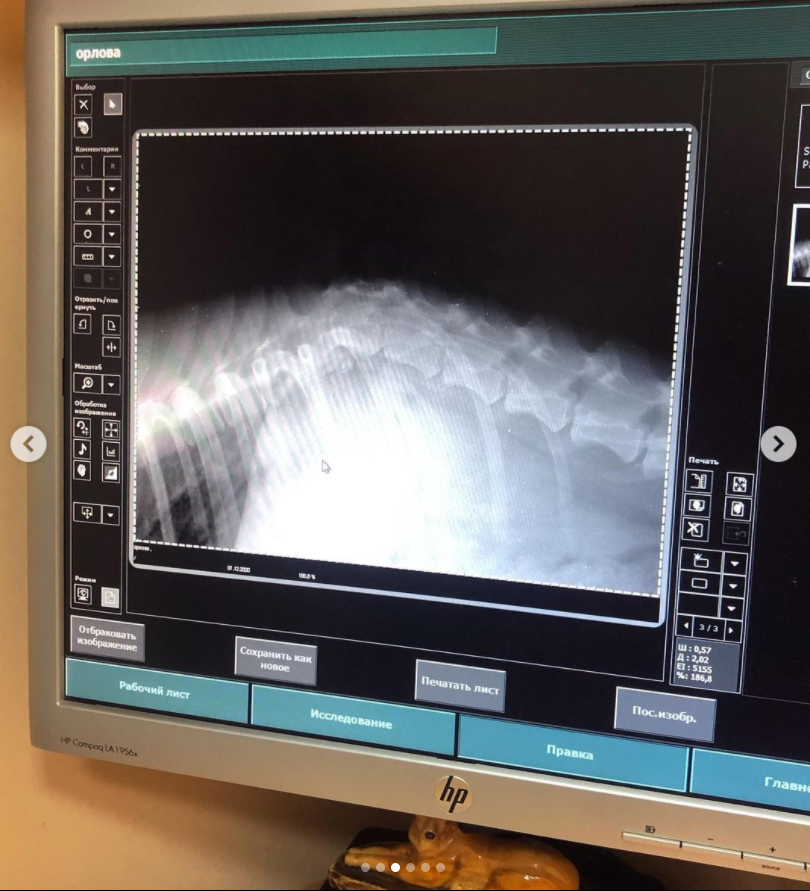

Після відвідин ветеринара авторка посту написала, що собака має шанс ходити, але для цього потрібно терміново робити операцію. Адже рентген показав перелом у грудному відділі хребта. В інакшому випадку – тварину довелось би усипити.